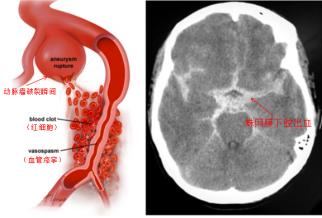

颅内动脉瘤并非真正的肿瘤,而是颅内动脉壁局部的异常膨出,就像血管壁上鼓起的一个“小气球” 或“小泡”。这个“小泡” 的壁通常很薄,随着血流不断冲击,它会逐渐变大,当压力超过壁的承受极限时,就会发生破裂,引发蛛网膜下腔出血。这种出血来势汹汹,约30%的患者会在首次破裂后便会直接失去生命,即使侥幸存活,也可能留下偏瘫、失语、认知障碍等严重后遗症,给个人和家庭带来沉重打击。